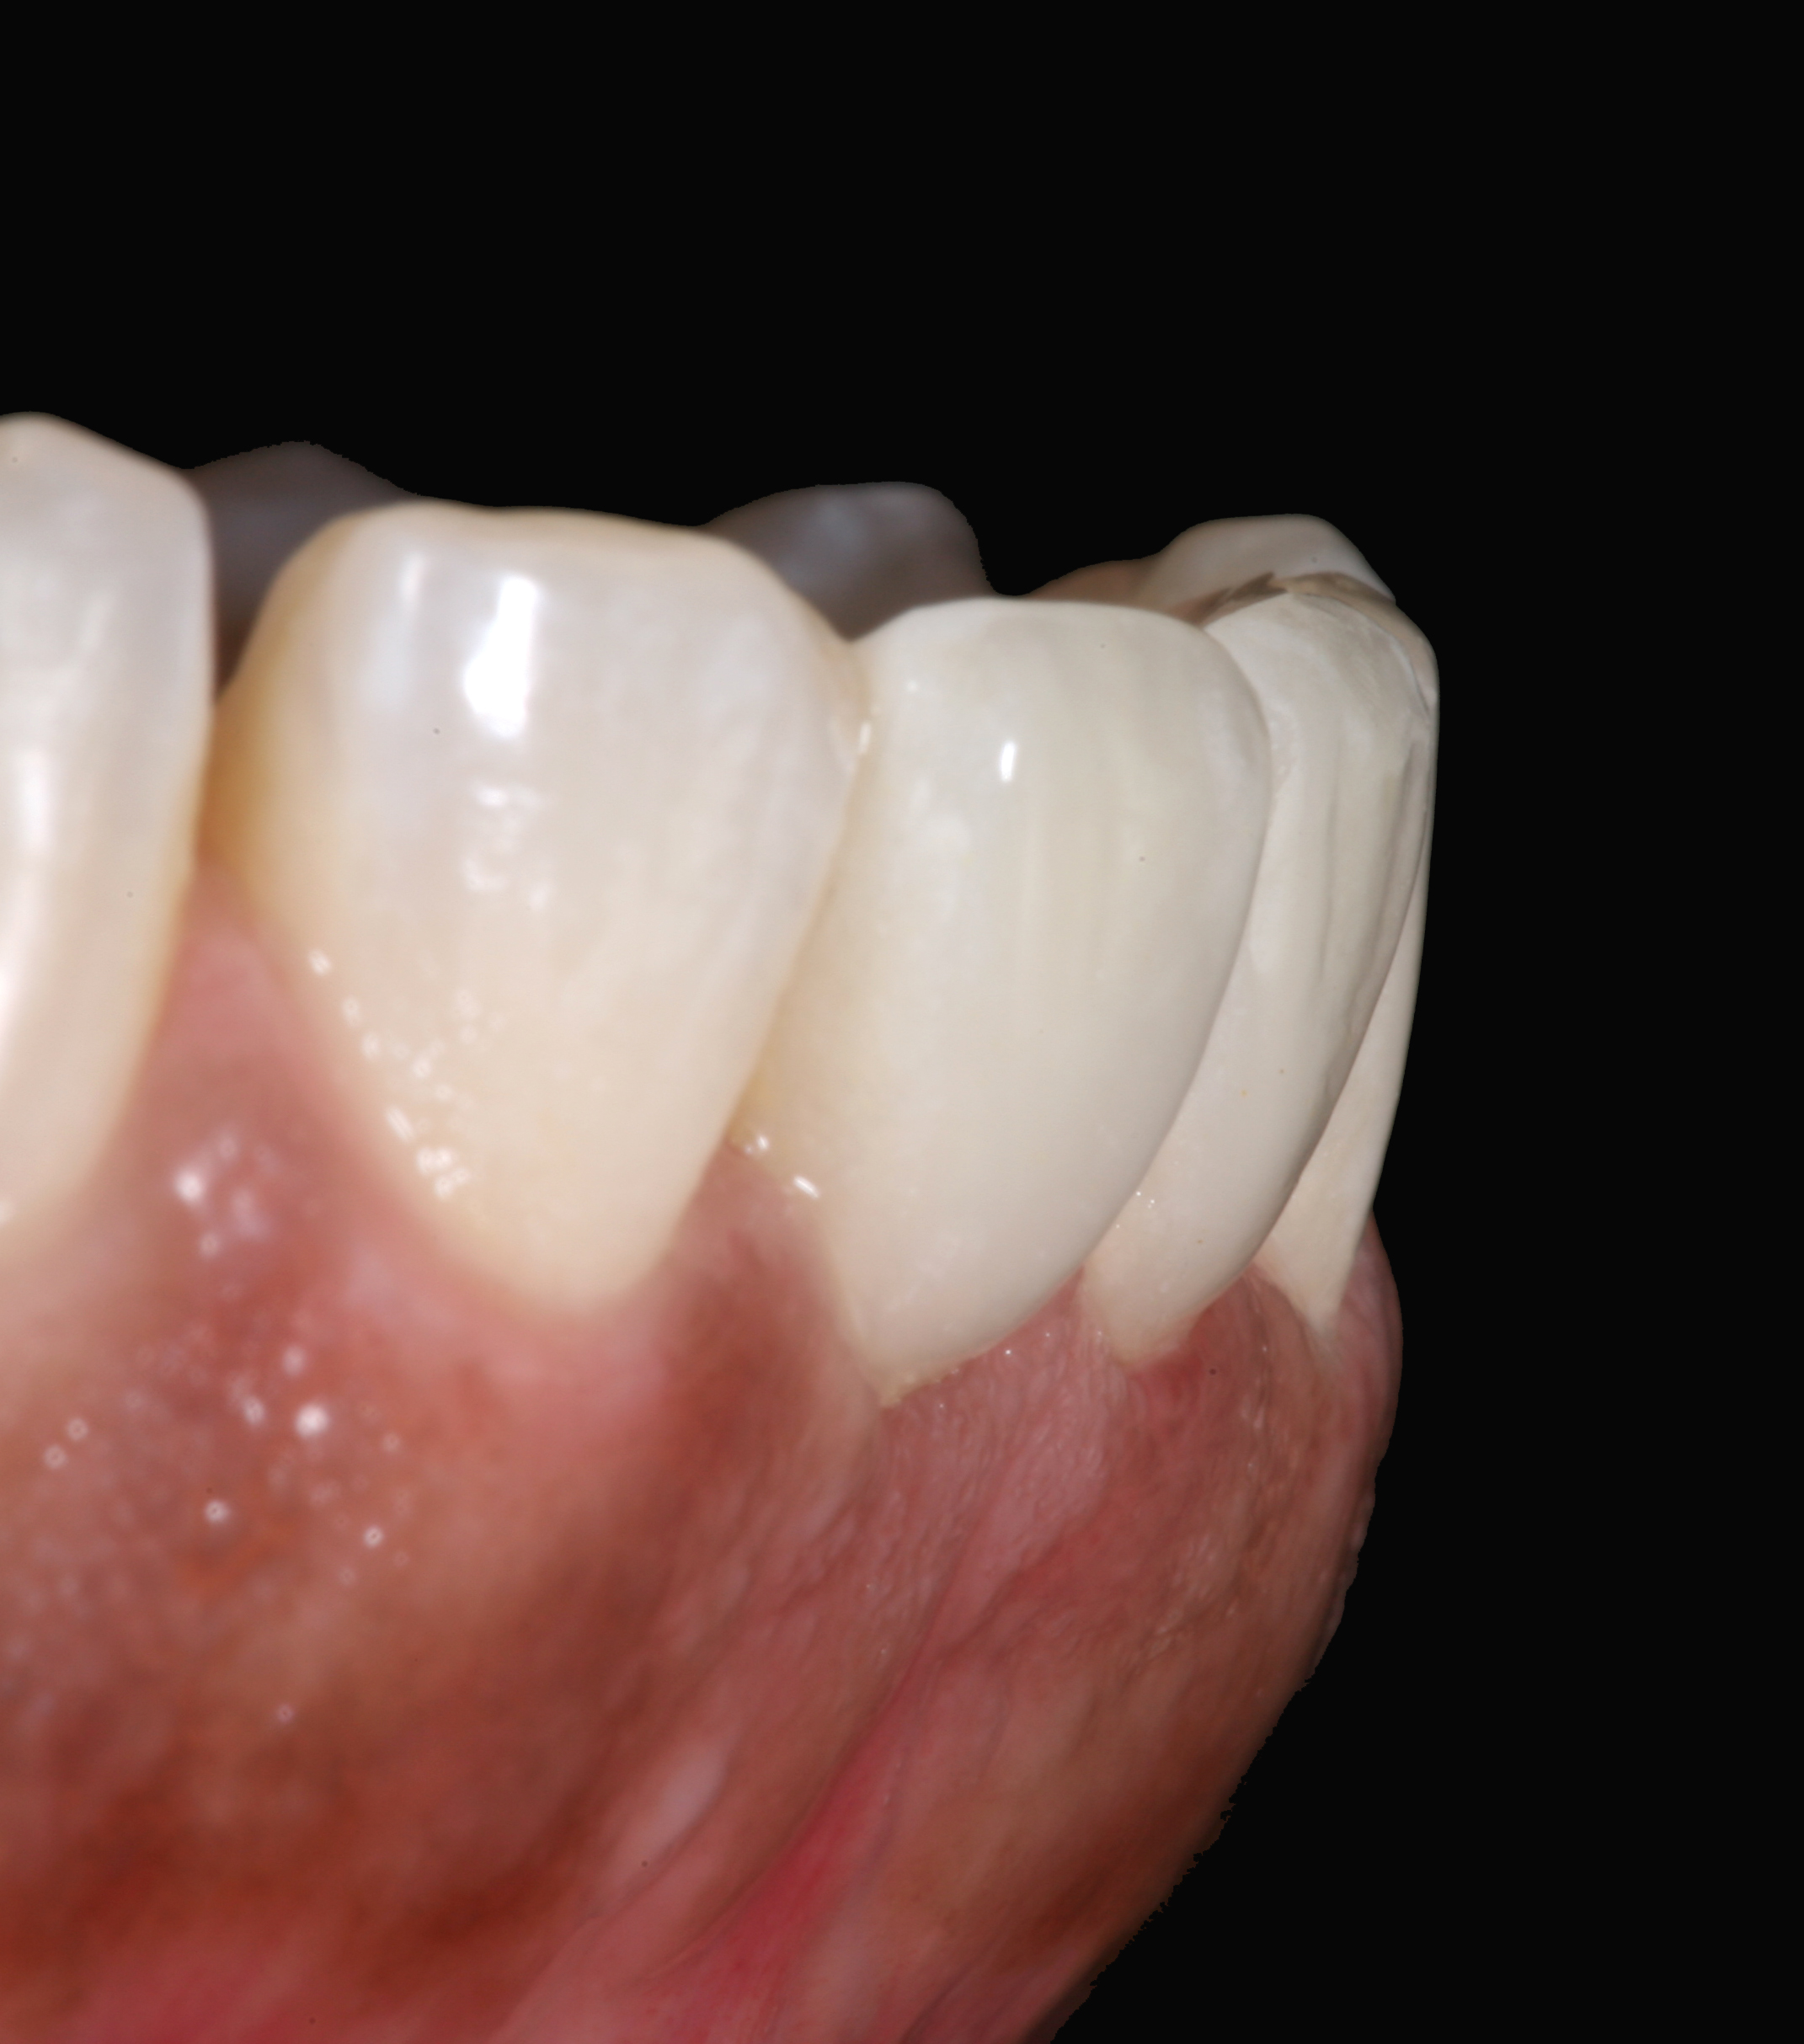

Postoperative situation: right lateral view.

Figure 12